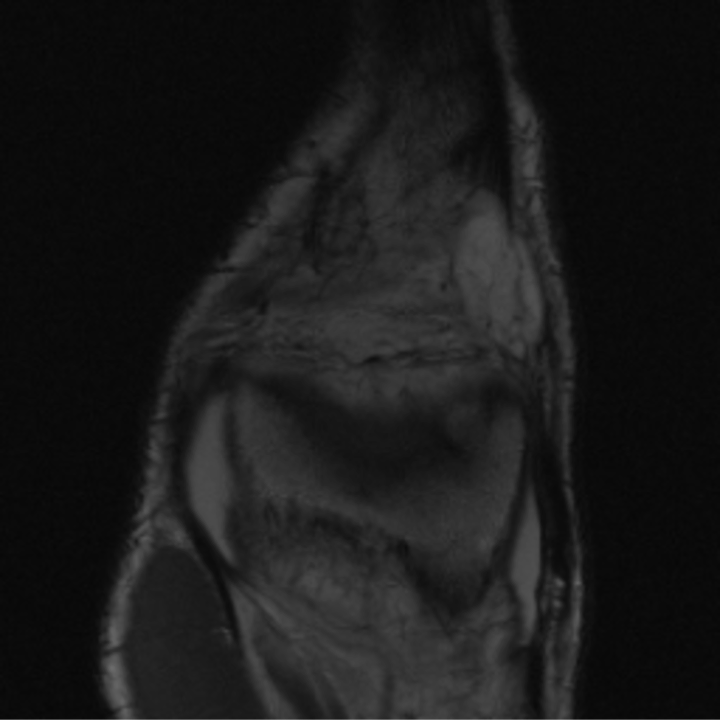

Preservation of Spine Curvature. For the spine segmentation on UK Biobank, we use a UNet++ model [83] with Dice Loss. We use a model trained to predict curves on DXA on UK Biobank [11]). We measure the Pearson correlation factor [11] of spine curvature measured on the generated MRIs where the input is a single MRI coronal slice, a single sagittal slice, or from the paired DXA, against the curvature of reference real MRIs of the same samples. The correlation coefficients are 0.89 for the coronal MRIs, 0.88 for the sagittal MRIs, and 0.87 for the DXAs on the test set of 308 human-annotated angles. We can then bin the curvature of the spines under different scoliosis categories based on human-annotated angles: mild: , moderate: , and severe . We show the results in Figure 8. This illustrates that the generated MRIs preserve the spine curvature from normal to severe scoliosis cases. Additional details about spine curvature are provided in supplementary material.

B.4 Preservation of Spine Curvature and Fat

For the spine segmentation on UK Biobank, we use a UNet++ model [83] with Dice Loss. We use a model trained to predict curves on DXA on UK Biobank [11]. We show in Figure IX that generated MRIs preserve the spine curvature from normal to severe scoliosis cases. We also study the case when DXA is used to generate the MRIs and show in Figure IX how the correlation to real curvatures compares to the input MRI case. The curvatures of the MRI generated from the coronal plane match the DXA curvatures more than the curvatures generated from sagittal MRI. This is expected since the antero-posterior plane of DXA is equivalent to the coronal plane for MRIs. This also explains the greater Pearson’s correlation coefficient of the coronal MRI (0.89) and DXA-generated curvature (0.88) compared to sagittal-generated curvature (0.87) relative to the reference curvature on the coronal plane. We observe though that MRI generation using X-Diffusion from another plane than the conventional plane for scoliosis assessment is valid.